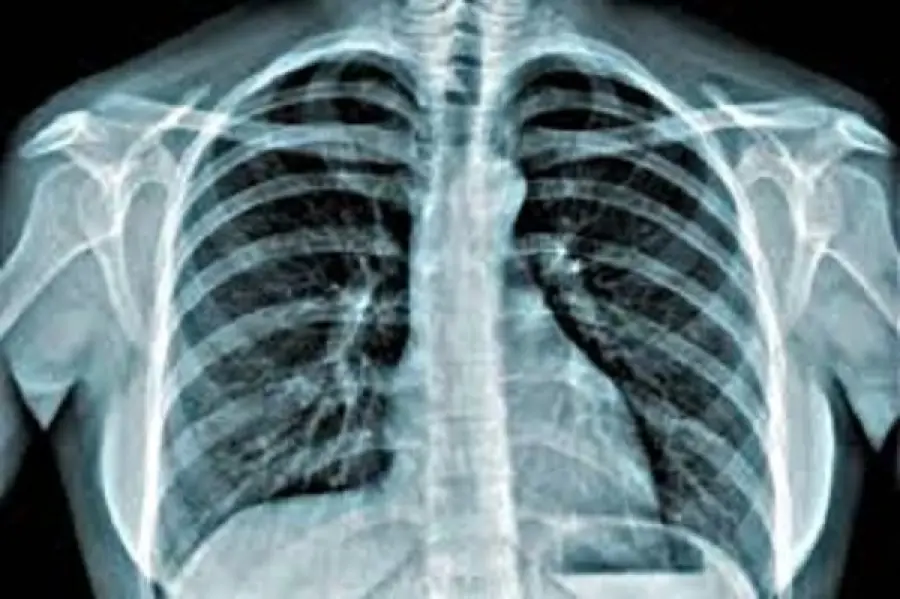

Illustrate durante un importante congresso a Verona le novità sulle terapie previste per il tumore al polmone. Premi per gli studi migliori sulle neoplasie toraciche polmonari condotti dai ricercatori italiani.

Protagonisti del congresso saranno i nuovi studi effettuati per il cancro al polmone, che nell’arco di questi ultimi anni sono stati effettuati dai ricercatori italiani. Nella conferenza saranno presentate le ultime novità edite durante l’incontro del Congresso mondiale IASLC tenutosi a Toronto e quelle enunciate durante il Congresso europeo ESMO, che è stato organizzato dal 19 al 23 ottobre scorso a Monaco.

La Fondazione finanzierà, come riportato da larena.it, gli studi clinici spontanei sulle neoplasie toraciche e polmonari. Inoltre, verranno premiati tutti quegli studiosi che più hanno contribuito alle nuove ricerche, attraverso soggiorni in centri oncologici sia italiani che esteri.

Antonio Santo elogia l’azienda ospedaliera universitaria integrata, presente stabilmente sulla città di Verona. Il presidente della Fondazione ha dichiarato che grazie all’impegno dei ricercatori e della Target therapy, la neoplasia, seppur rimanente una delle più gravi e diffuse, si avvia verso soluzioni sempre più curabili.